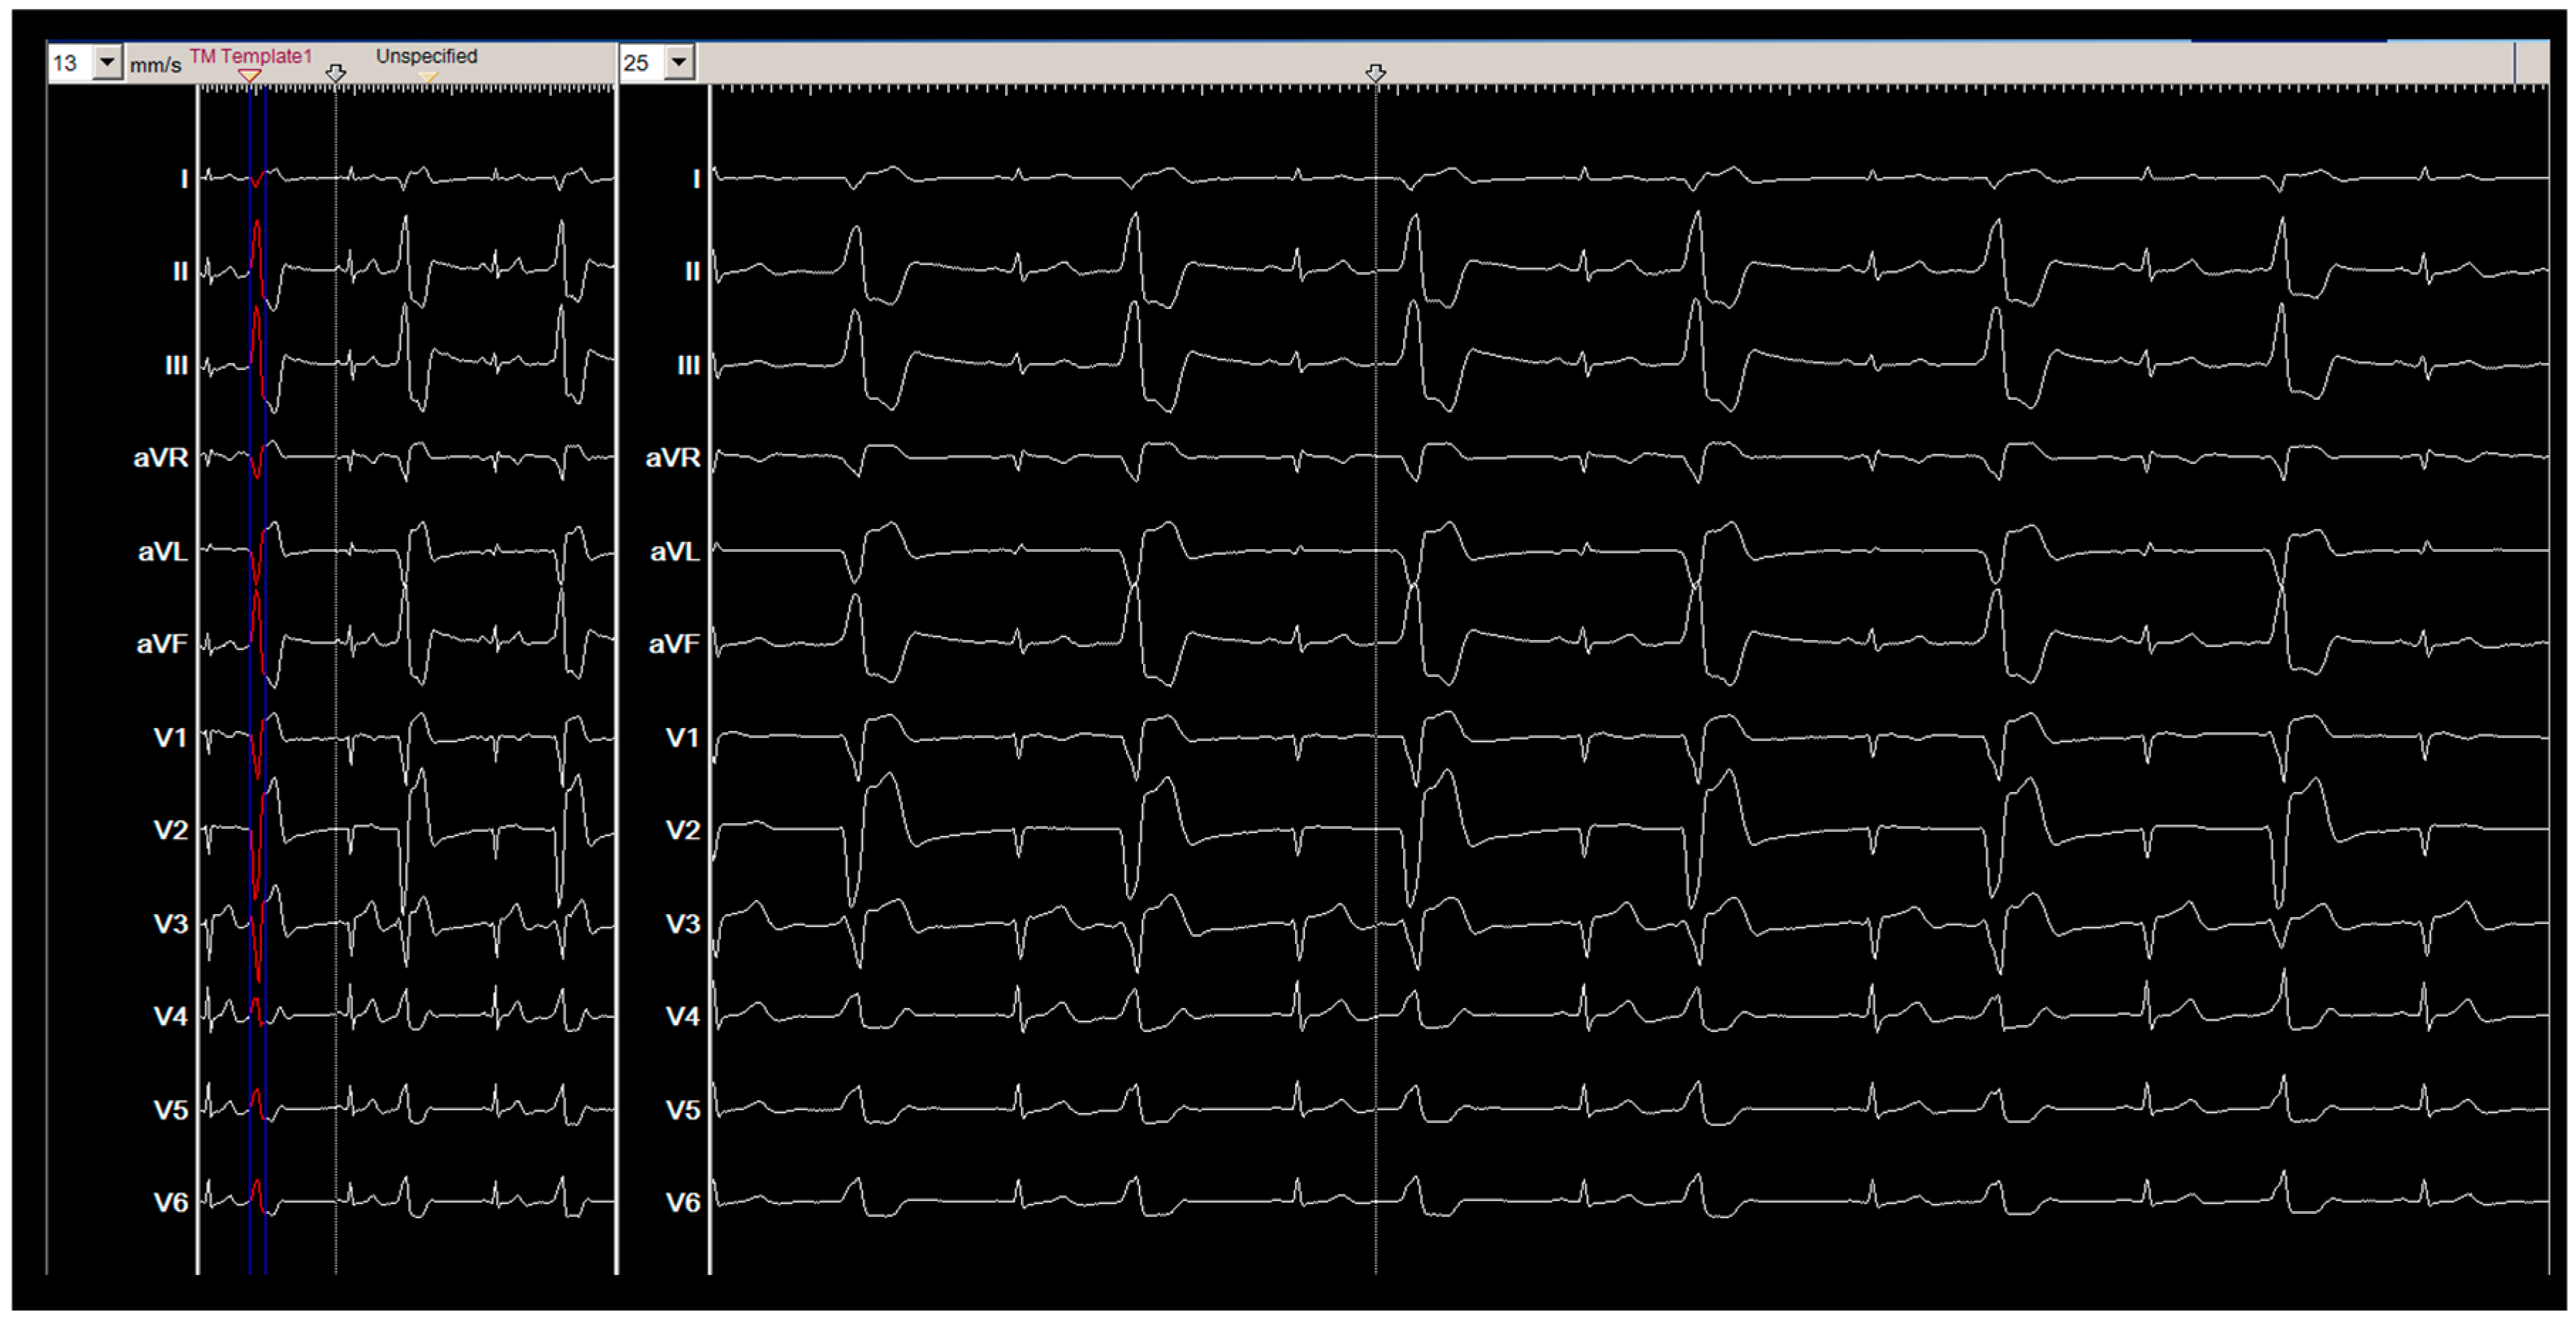

2. Method and Results